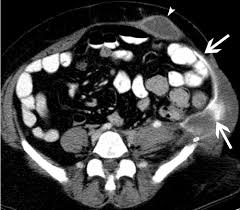

More important CT findings can be used to diagnose unsuspected hernias and to distinguish hernias from masses of the abdominal wall such as tumors hematomas abscesses undescended testes and aneurysms. Cross-sectional CT scans can show hernias and the contents of the peritoneal sac. No advice on which is better but I will tell you my experience.

Abdominal Wall Hernias Imaging Features Complications And Diagnostic Pitfalls At Multi Detector Row Ct Radiographics